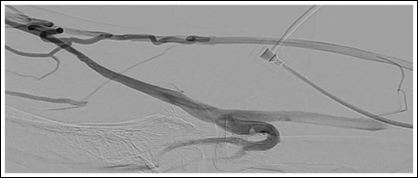

Figure 4: Stenosed segment of the cephalic vein of the upper arm (}).

We examined the angiography again and identified a stenosed segment of the cephalic vein at the distal upper arm. Regarding to the missing well-developed collaterals maintaining venous out flow before the fistula was at risk for occlusion. Hence, we performed surgical revision of the stenosis using an interposition graft (PTFE 6 mm). This segment showed post thrombotic lesions as well with trabecular morphology. The flow rate measured 550 ml/min and there was continuous thrill in the fistula. The temperature of the hand was warm, and pulses were palpable at the wrist.

Catheter angiography shows vascular anatomy of the fistula with out flow obstruction at the upper arm cephalicvein (Figure 3) and well-developed collaterals (Figures 1 and 4). Troubleshooting was not such as adequate as we did appreciate preexisting problems in this case. Figure 1 demonstrates primary flow is drained through the collateral in the basilic system. Figure 2 shows inadequate drainage into the deep venous system through elbow perforator with lesions in upper arm cephalic vein and non-visualization of median cubital vein.